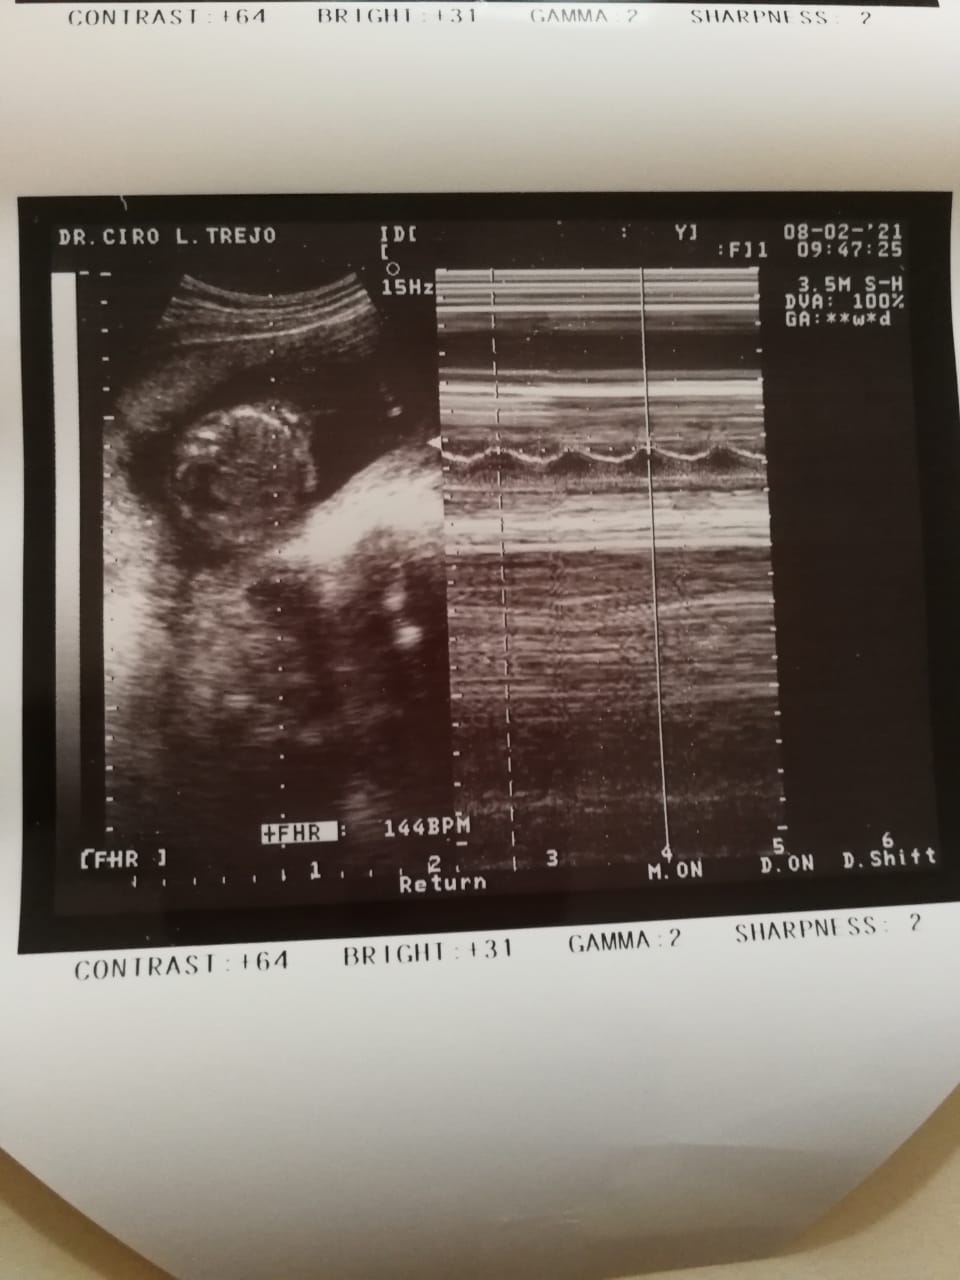

I’ve been pregnant four times. Each time we found out, we were overjoyed—filled with hope and excitement. But that happiness was always cut short. Every single pregnancy ended in miscarriage. The pain is indescribable. Each loss sent me into a deep depression, grieving the baby we had already begun to love. Through it all, my husband has been my rock, holding me up and reminding me not to give up on our dream.